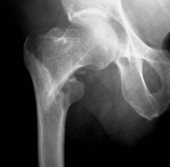

Typische pertrochantäre Femurfraktur